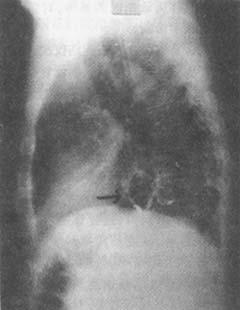

照片名称:胸椎压缩性骨折